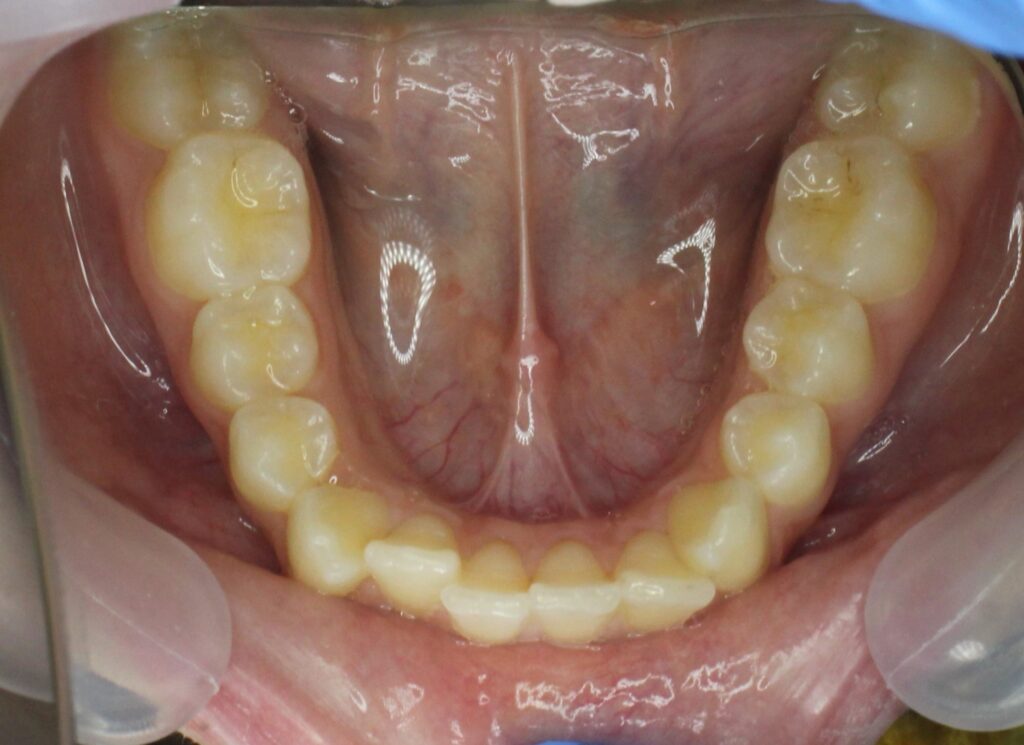

пациент до лечения брекетами